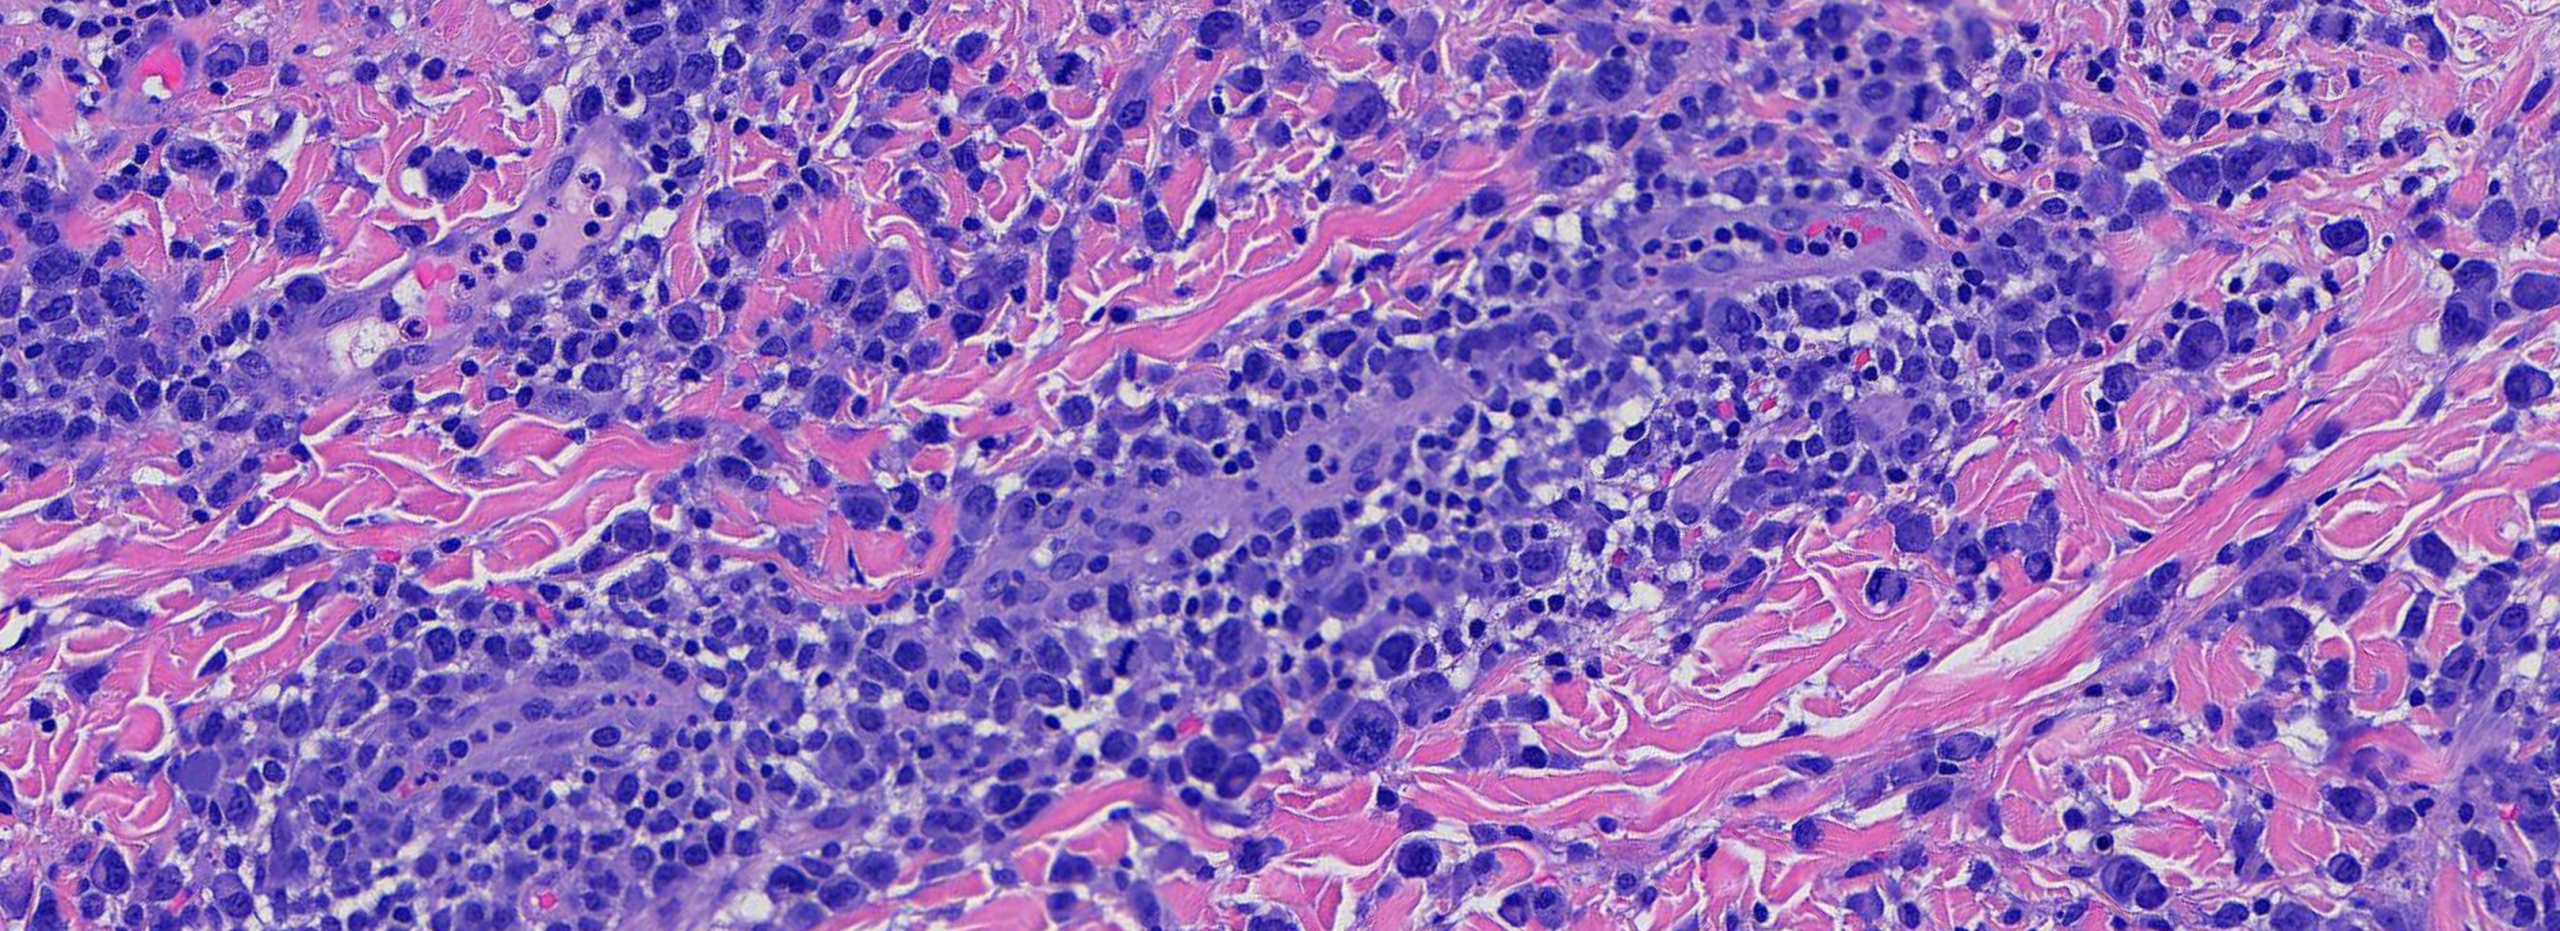

(Image 3 & 4: High power showing large, atypical mononuclear cells with pleomorphic nuclei.)

The combination of large atypical CD30+ mononuclear cells with pleomorphic hyperchromatic nuclei, set within a mixed inflammatory perivascular infiltrate, coupled with a clinical history of recurrent self-healing papulonodular lesions that wax and wane over months to years, is diagnostic of Lymphomatoid Papulosis. Critically, this diagnosis cannot be made on pathology alone — clinicopathologic correlation is paramount.